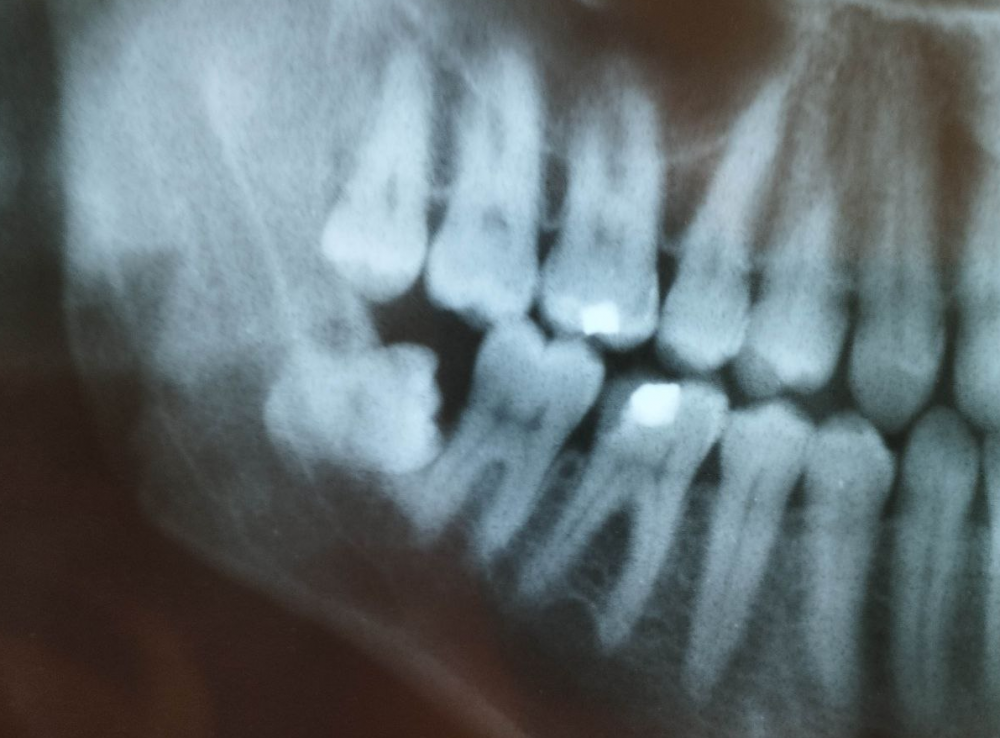

3убастик Опубликовано 27 мая, 2023 Поделиться Опубликовано 27 мая, 2023 Здравствуйте, подскажите как быть. Удалили сложную ретинированную восьмерку снизу, по причине что начала гноиться десна, зуб был в порядке. 10 дней лунка обрабатывалась ванночками из хлоргексидина после еды и еще несколько раз в промежутках. Спустя 10 дней, поняв что лунка не заживает, 10 дней в лунку закладывался левомеколь 3 раза в день на 20 минут на кусочке бинта (сам себе назначил по советам из интернета), убедившись что ничего не меняется на 23 день после удаления пошел к врачу, где был обнаружен небольшой альвеолит. Лунка была промыта хлоргексидином, врач вымыл остаток кровяного сгустка, назначил асепту, которая закладывалась в лунку по 2-3 раза в день. Через 3 дня был повторный осмотр с промыванием лунки, она оказалась чистой, продолжил закладывать асепту (14 дней), лунка особо не заживает до сих пор (сегодня 38 дней после операции и 15 дней как закладываю асепту), сделал повторный снимок, сходил еще раз на осмотр, врач сказал что стало немного получше, кюретаж не требуется, предложил продолжить до месяца использовать асепту и ждать пока затянется. В последние пару дней пару раз после закладывания асепты щипало в лунке минут по 10-15, до этого не было такого. Другой хирург посоветовал закладывать солкосерил, но меня смущает что через это лекарство может передаться болезнь Крейтцфельда-Якоба, которая аукнуться может через 5-15 лет и закончиться очень плачевно, плюс сам солкосерил сейчас стоит космических денег - за 5 г. тубу около 5 тысяч рублей. Подскажите, стоит ли использовать солкосерил, или может есть какие-то безопасные препараты для ускорения эпителизации? Прикладываю снимки до и после, плюс фото самой лунки, может кто на снимках что увидит почему не затягивается. И еще вопрос, на 7 зубе это что за вмятинка, отметил стрелкой на фото? Не может быть повреждения во время операции? Сверлили много... До удаления: После удаления: Лунка: Ссылка на комментарий